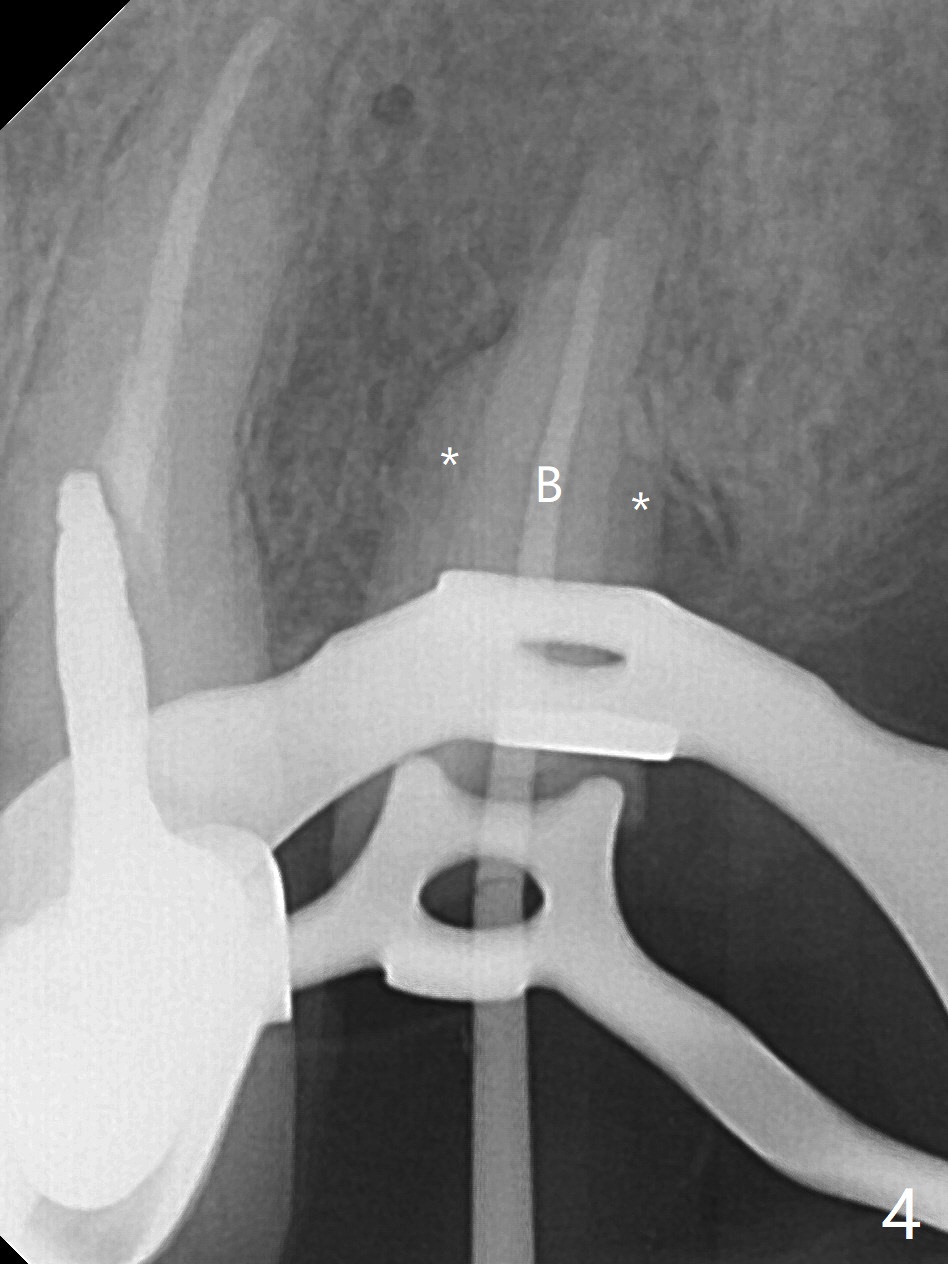

为了美观,病人希望先进行下颌治疗,当他回来时,提到左上肿胀,但是没有明显疼痛。去除左上4-8桥,发现4仍可以保留(图一,二),8龋齿龈下(图三)。4根管治疗只发现颊侧根管(图四:B),腭侧根管好像闭锁,与CT一致。放置氢氧化钙糊剂,明天病人回来治疗,术后两周。我的疑问是,如果肿胀消失,仅完成颊侧根管充填,治疗够吗?什么时候可以安置球状牙桩?如果肿胀没有消失,怎么搞通腭侧根管?